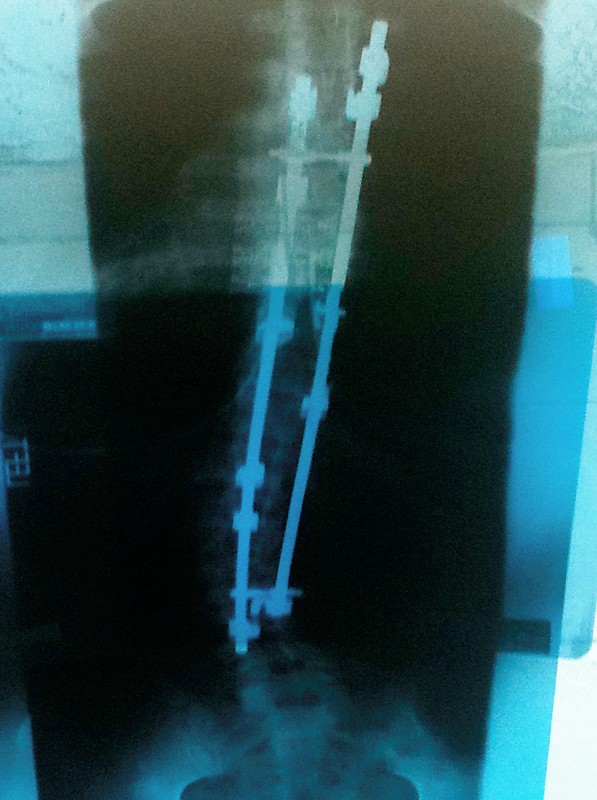

As a young girl, Gina was diagnosed with severe scoliosis, or curvature of the spine, that caused significant pain. An athlete, she fought through it to continue playing sports in college until the pain became just too much. At 20, she had a long spinal fusion, an operation that permanently connected all the thoracic vertebrae and most of the lumbar vertebrae into one solid structure in her body.

For more than 15 years, the surgery gave her some improvement, but she still lived with nagging, achy muscle pain. Then about five years ago, she began to experience extreme nerve pain shooting down her legs, impairing her ability to walk and perform her job as a Senior Food and Drug Investigator for the state of California. She scheduled an outpatient procedure—spinal decompression surgery—meant to alleviate her nerve pain.